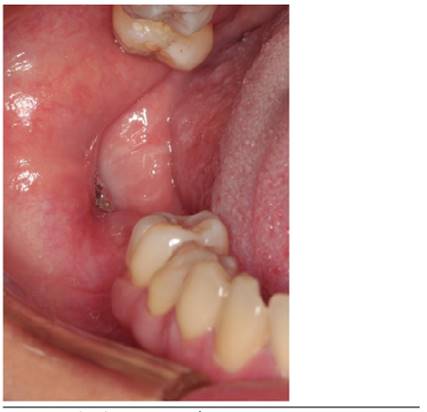

En julio de 2014 se presenta en el Servicio de Cirugía Maxilofacial del Hospital Clínico San Borja Arriarán una paciente de sexo femenino, 46 años, con un aumento de volumen mandibular derecho comunicado a boca a través de una perforación de la mucosa generada hace tres años al momento de la extracción del tercer molar (Figura 1 y 2). Al examen imagenológico (Radiografía y Tomografía) presenta una gran zona radiolúcida que compromete cuerpo y rama mandibular (Figura 3).